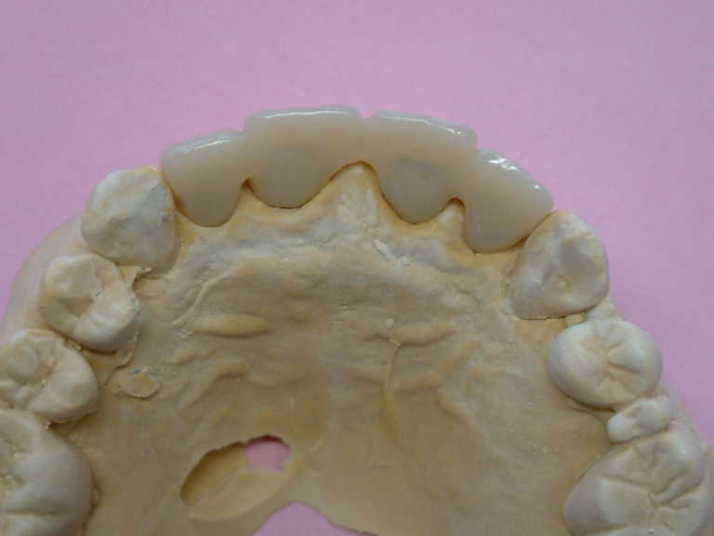

☆2.2の歯の幅を広げ、1.1の幅を狭くし

全体のバランスを取り作りたいと思います

☆1〜1の間の歯間空隙部分が不自然にならない

よう歯肉模型にて確認しながら製作します |

補綴物物 完成

模型上では、1.1下部孤形空隙が広いように

見えますが、歯肉模型にて調整して

歯肉を圧迫せず、息が漏れることが無いように

調整しました |